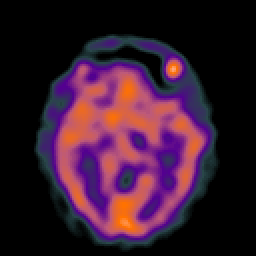

Hypertensive Encephalopathy, overlay -- Slice #11

[Home][Help][Clinical] Slice 11